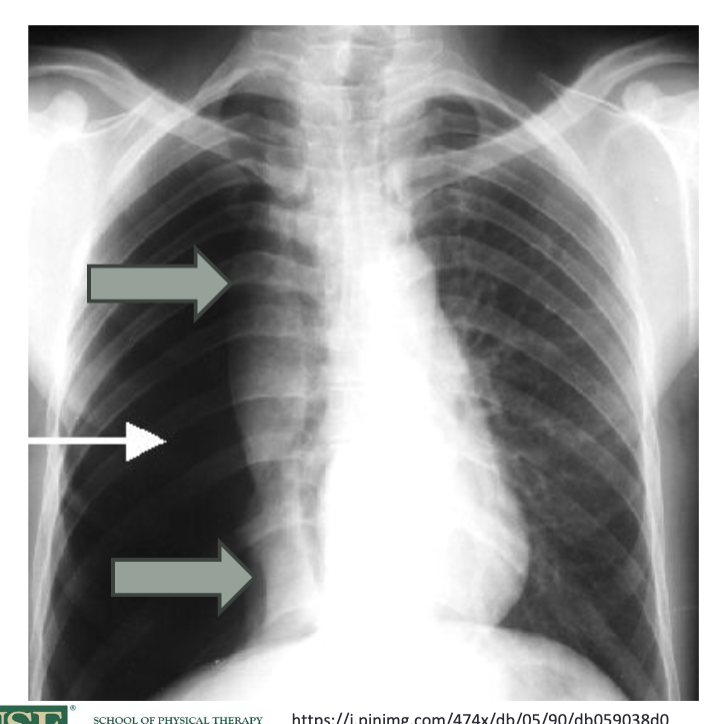

what does a pneumothorax look like?

since there is air in the pleural space, see a collapsed lung and increased radiolucency on the affected side of the chest x-ray- structures will be pushed away from the affected side and a shift of the mediastinum